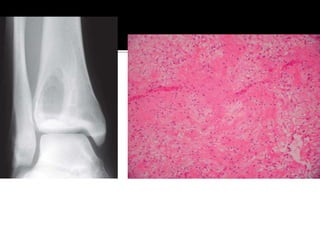

 Developmental/reactive lesion

 1st – 2nd decades. M:F = 2:1

 Any extremity; most common – proximal

humerus and femur. Ilium and calcaneum.

 Active during skeletal growth and heal

spontaneously at maturity

 Asymptomatic unless pathological fracture

 Radiologically – Centrally located, purely

radiolucent lesion which concentrically

expands the cortex. No cortical destruction

 Cyst filled with straw colored fluid.Thin

fibrovascular lining.

 Observation

 Aspiration

 Injection of steroids/bone marrow/bone graft

substitutes

 Curretage